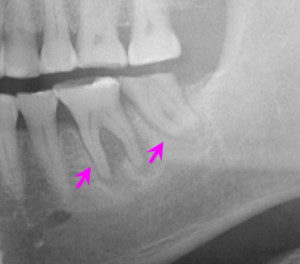

右下インプラント埋入直後のレントゲン写真です。

矢印部に下顎内の神経があり、これを避け、隣の歯と十分距離が保てるような位置でインプラントを埋入できました。